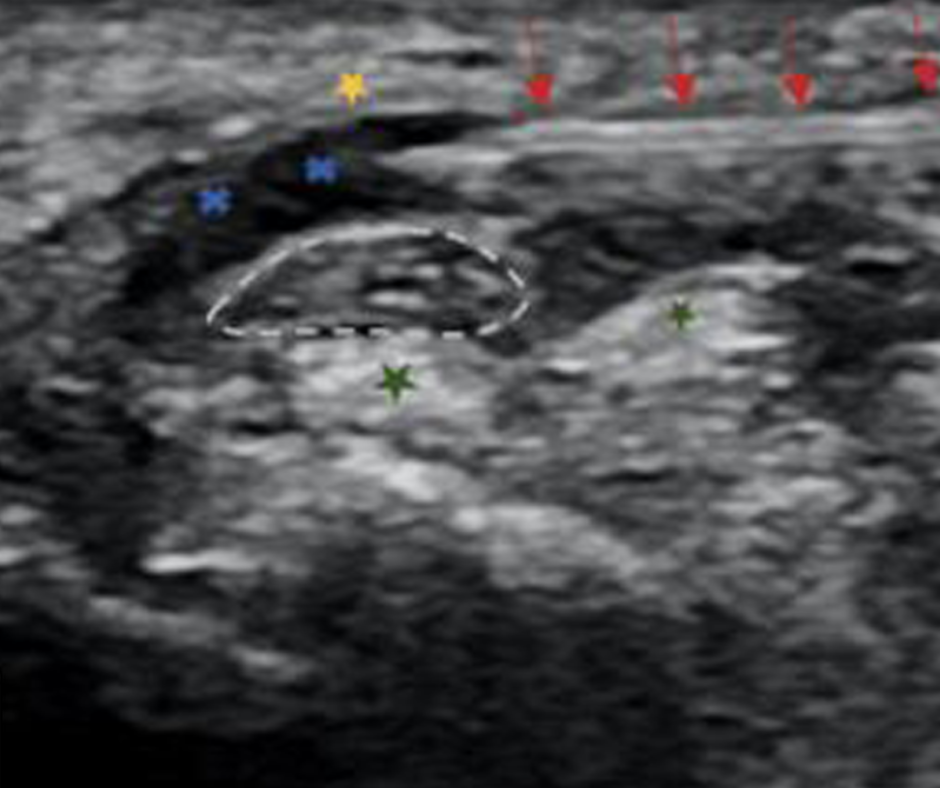

Pour évaluer la douleur et les symptômes d’un patient avant et après la procédure, les chercheurs ont utilisé le Boston Carpal Tunnel Questionnaire (BCTQ; symptômes et fonctionnel) et l’échelle visuelle analogique (EVA), et ont examiné les résultats de la section transversale du nerf médian à l’échographie. Le suivi a été complété à quatre semaines, 12 semaines et six mois.

Les chercheurs ont également constaté une réduction significative de la section transversale des nerfs médians à l’échographie dans les deux groupes d’anatomie aqueuse, notant une réduction de 43% pour le premier groupe et de 46% pour le deuxième groupe, par rapport à un 11 pourcentage de réduction pour le troisième groupe. Aucun effet indésirable significatif n’a été signalé.